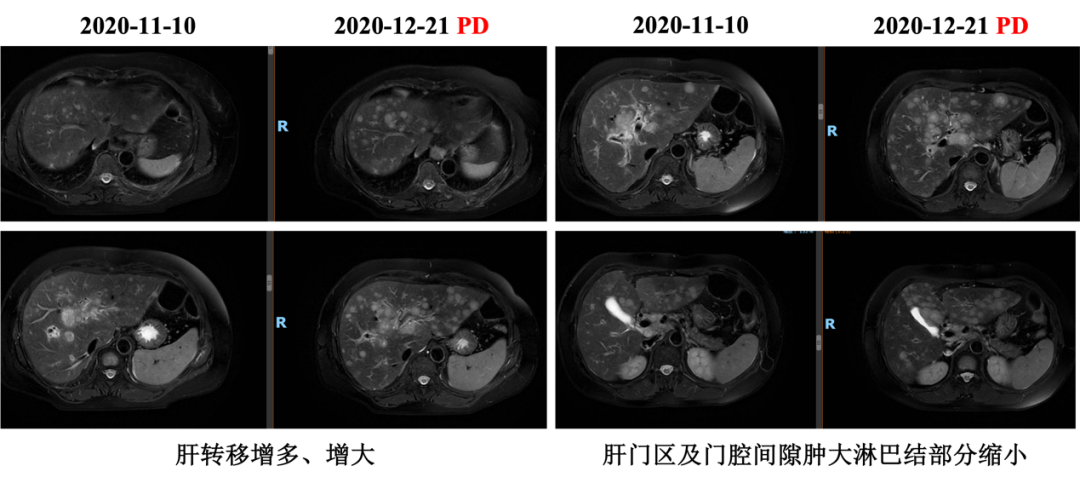

入组MO28231临床试验,于2016-12-1开始行T-DM1治疗,具体:T-DM1 3.6mg/kg 237.6mg d1,Q21d。最佳评效PR。肝门区淋巴结自2019-6出现,逐渐增大,2019-11增大至29*22mm,考虑转移,判定为新发病灶PD出组,共治疗48周期,PD时间为2019-6,PFS为30月。不良反应:胆红素升高1级,血小板下降1级,疲劳1级,鼻出血1-2级,关节僵硬1级,手足麻木1级。

图4. 三线治疗